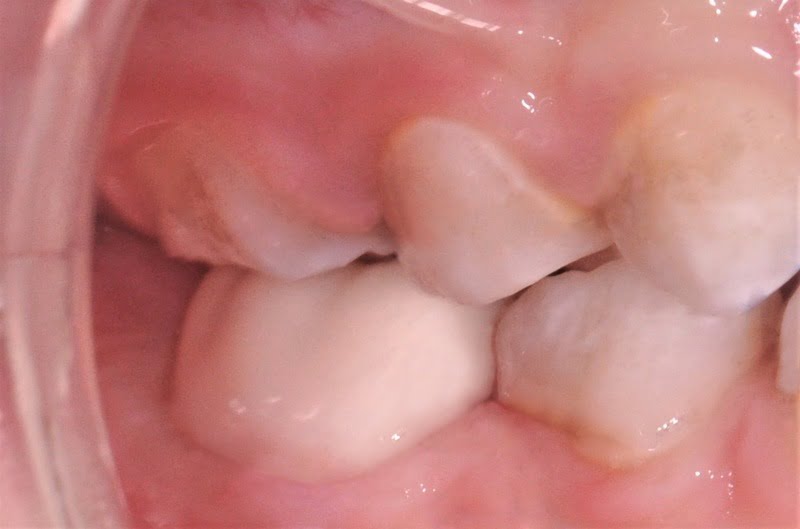

Após limpeza da superfície dentária e controlo hemorrágico dos tecidos gengivais, a coroa de zircónia do tamanho previamente selecionado foi cimentada com um cimento resinoso (RelyXTM Unicem2 Automix, 3M ESPE) (fig. 9). Todos os excessos de cimento foram cuidadosamente removidos com recurso a sonda e fio dentário. Na mesma sessão foi também realizada uma restauração em compósito na parede distal do dente 84 (fig. 9).